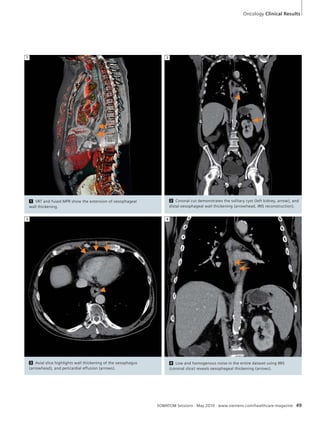

Oncology

46 3D Guided RF Ablation and CT

Perfusion – a New Combination for

Monitoring of Treatment Response

48 SOMATOM Definition Flash:

Routine Re-staging of Oesophageal

Carcinoma Utilizing IRIS Technology